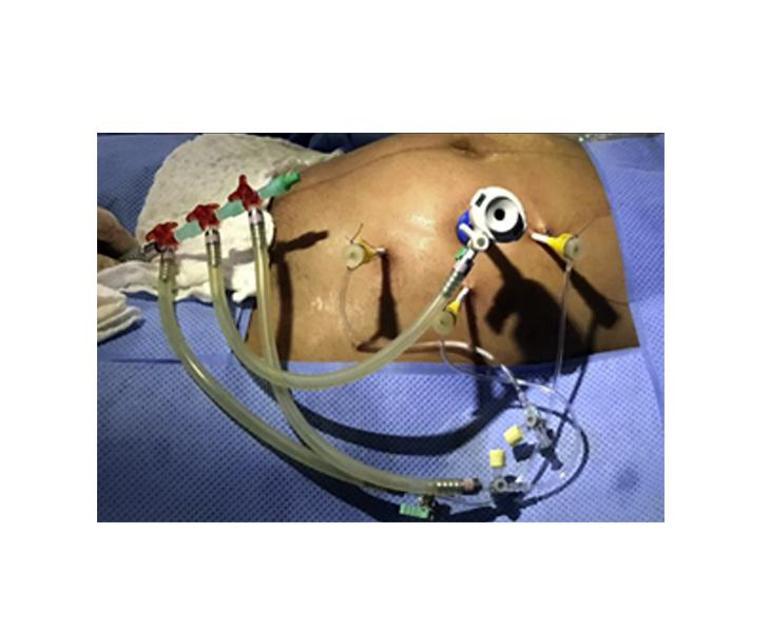

Spina bifida için fetal cerrahi günümüzde üç teknikle yapılıyor. Bunlardan ilki, histerotomi ile açık fetal cerrahi olarak adlandırılıyor. Rahim sezaryen ameliyatındaki gibi dışarı alınıp rahime kesi yapılarak bebeğe ulaşılıyor. İkincisi fetoskopi ile kapalı fetal cerrahi. Rahim dışarı alınmadan fetoskopi aletleri annenin cildinden direkt rahim içine yerleştirilerek gerçekleştiriliyor. Bir de laparatomi asiste fetoskopik cerrahi adıyla bilinin hibrid yöntem bulunuyor. Burada da rahim açık ameliyattaki gibi dışarı alınıyor ancak rahme kesi atılmadan fetoskopi aletleri rahim içine yerleştirilerek ameliyat yapılıyor. Prof. Dr. Büyükbayrak, histerotomi ile açık fetal cerrahi yapılan hastaların rahimde bir kesi ve dikişler olduğu için sadece sezaryen yöntemiyle bebeklerini dünyaya getirebildikleri ancak laparatomi asiste fetoskopik cerrahi (hibrid yöntem) ve fetoskopi ile kapalı fetal cerrahi yapılan hastaların yaklaşık yüzde 75’inin sezaryenla doğum yaptığını, yüzde 25’inin de vajinal yolla doğurabildiğinin altını çizdi.

"Her cerrahın bir ameliyatta tek bir hastası varken, bizler hem anneyi hem de bebeğini gebelik devam ediyorken ameliyat ediyoruz. Çok titiz ve ciddi bir ekip çalışması gerektiren bu ameliyatı ilk kez yaptığımız ve başarılı bir şekilde tamamladığımız anı hiç unutamam. Ekip olarak her ameliyatımızın başarılı olmasını ve bebeklerimizin sağlıkla doğmasını en az aileleri kadar canı gönülden istiyoruz ve bunun için elimizden geleni yapıyoruz."